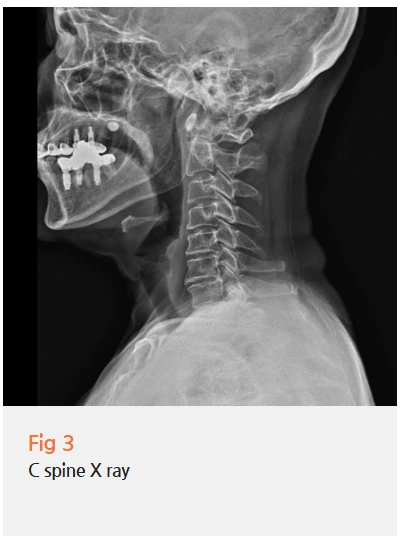

그래서 뇌 MRI, MRA, 그리고 목 엑스레이까지

포괄적인 검사를 진행했습니다.

검사 결과를 보니, 삼차신경통의 가장 흔한 원인인

신경혈관압박은 명확하게 관찰되지 않았어요.

하지만 경추부,

즉 목에 구조적인 문제가 있다는 걸 확인할 수 있었습니다.